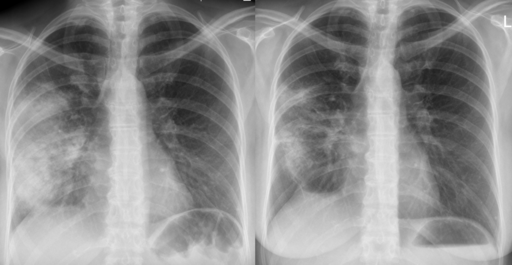

Chest X-ray

A definitive diagnosis of CAP requires evidence of consolidation on a chest x-ray (CXR). Therefore, it is recommended to perform a CXR for all patients admitted to hospital as soon as possible, ideally within 4 hours of admission.

Radiographic image of pneumonia before (left) and after (right) antibiotic therapy

Acute pneumonia

Hellerhoff, CC BY-SA 3.0, via Wikimedia Commons